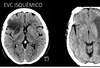

imagen

A

TC y RM

Q

Características de RM para evc isquemico

alta sensibilidad y especificidad en fase aguda

21

q permite detectar secuencia de difusión de RM

infarto en minutos evc isquemico